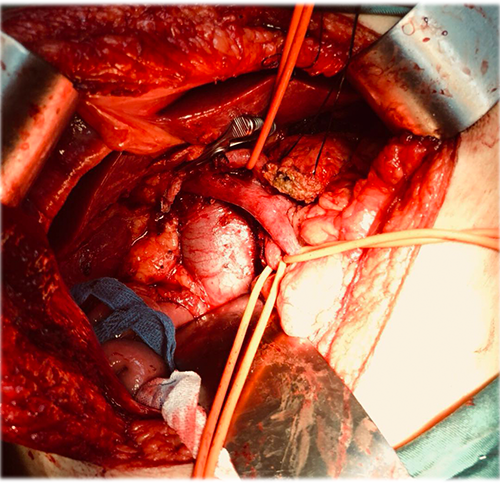

胰头腺癌---胰十二指肠切除